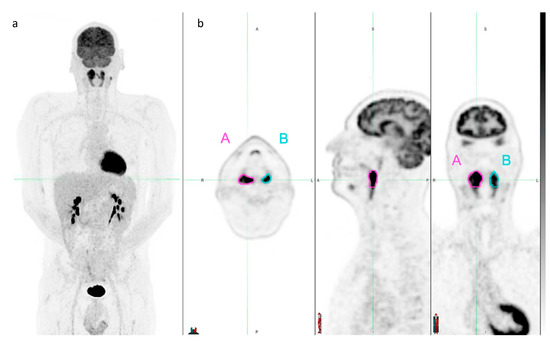

2.3. Image Segmentation and Radiomic Features’ Extraction